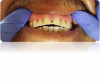

Tooth erosion from GERD occurs as a result of exposure of the teeth to hydrochloric acid from the stomach. This erosion, in conjunction with abrasive factors such as tooth wear, mastication, toothbrushing, etc, typically manifests as ditching or cupping of teeth on the incisal edges and lingual surfaces of the maxillary anterior teeth and the cusps of the occlusal surfaces of both maxillary and mandibular posterior teeth. This "ditching" effect is different than a patient ingesting large quantities of carbonated beverages, which typically results as erosion of the labial or facial surfaces of the anterior teeth (Figure 7). The lesions caused by GERD are hard to the touch with an explorer instrument, as opposed to decay.14

Fig 7. Erosion of the facial maxillary central incisor.

Figure 7